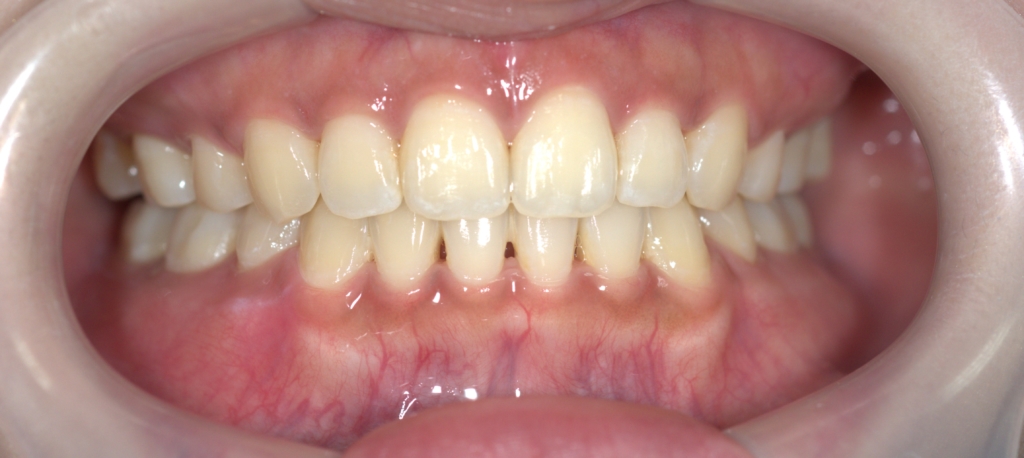

【After】

【保定】 上下ともフィックスタイプ&クリアリテーナー

【治療期間】 約2年間

【治療費用】 83万8千円

顔面偏差値という言葉に驚きながら、始めた矯正治療です。

「マスクを外しても気持ちよく過ごせます!」と満足してもらえたようで何よりでした。